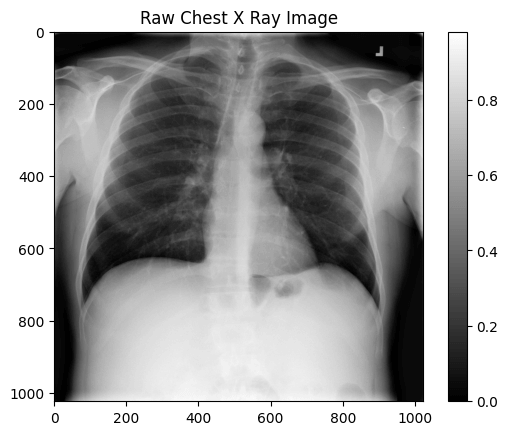

img_dir = '/images/images-small/'

img = train_df.Image[0]

image = plt.imread(os.path.join(img_dir, img))

plt.imshow(image, cmap='gray')

plt.colorbar()

plt.title('Raw Chest X Ray Image')

print(f"The dimensions of the image are {image.shape[0]} pixels width and {image.shape[1]} pixels height, one single color channel")

print(f"The maximum pixel value is {image.max():.4f} (white) and the minimum is {image.min():.4f} (black)")

print(f"The mean value of the pixels is {image.mean():.4f} and the standard deviation is {image.std():.4f}")

# The dimensions of the image are 1024 pixels width and 1024 pixels height, one single color channel

# The maximum pixel value is 0.9804 (white) and the minimum is 0.0000 (black)

# The mean value of the pixels is 0.4796 and the standard deviation is 0.2757

It's an image with a 1024x1024 dimension, black and white.